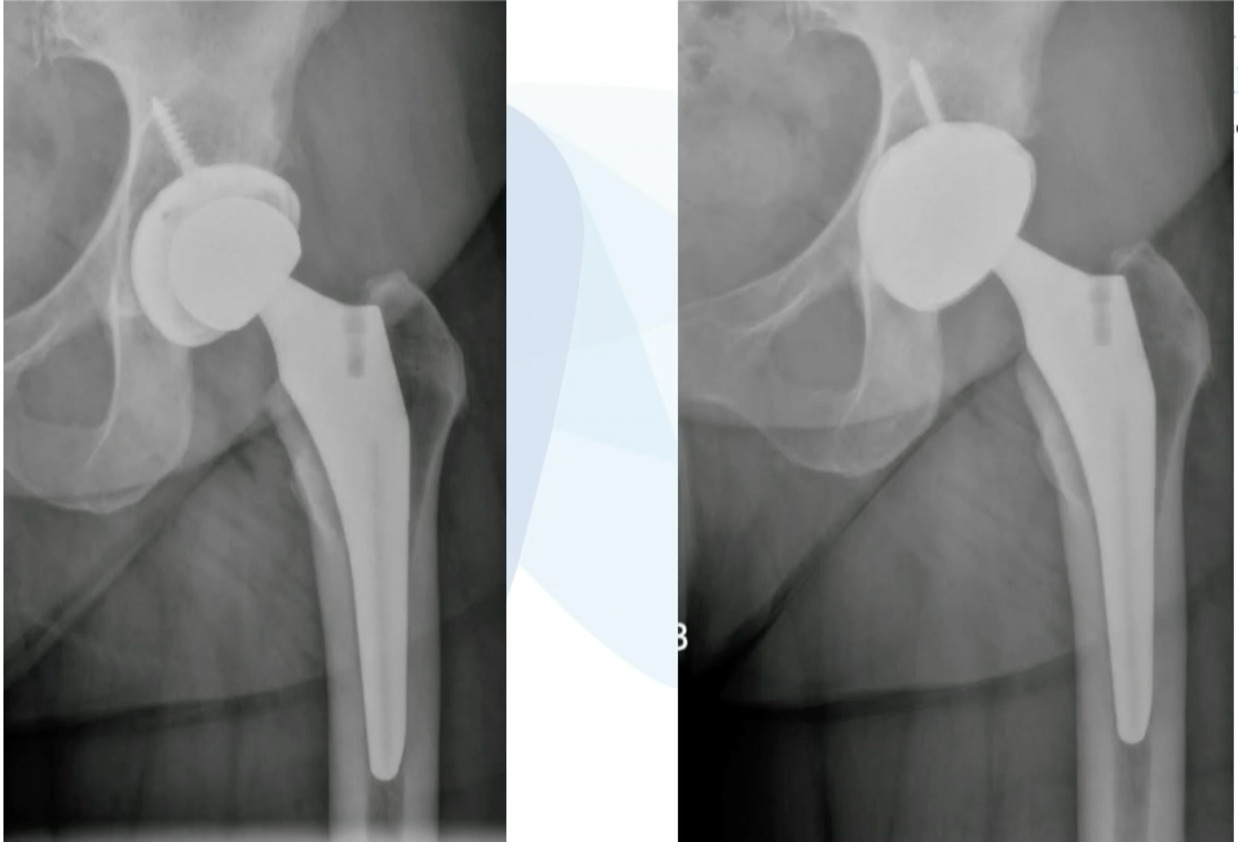

We’ve done this on quite a few cases and this is working really well, but you don’t have to use a primary stem, you can use a revision stem. But these loose components are ideal for the ASC setting. This was an ileus-psoas impingement. (Figure 5)

Cup was revised. This is an excellent case to do in the ASC setting.